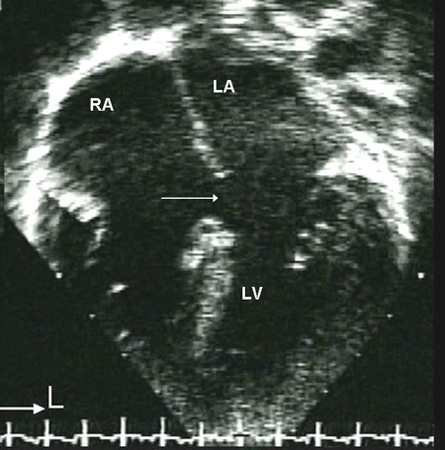

Imagen de ecocardiografía de 4 cámaras apical de una comunicación interauricular (CIA) de tipo ostium primum (flecha). (AD) aurícula derecha; (AI) aurícula izquierda; (VI) ventrículo izquierdo